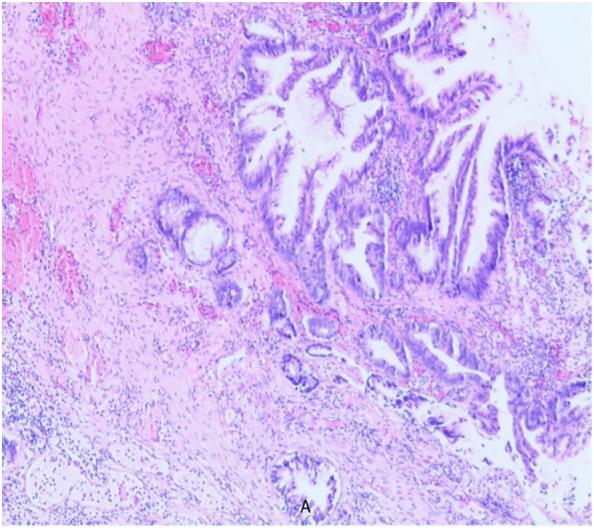

前列腺黏液腺癌伴极低前列腺特异性抗原水平及复发性疾病:一例报告

Mucinous adenocarcinoma of the prostate with extremely low prostate-specific antigen levels, recurrent disease: a case report.

Mucinous adenocarcinoma (MC) is a very rare type of prostate cancer, accounting for less than 1% of prostate adenocarcinomas, and its etiology is still unclear. Its clinical symptoms are similar to those of prostate hyperplasia and follicular carcinoma of the prostate, which are often misdiagnosed, and a definite diagnosis depends on pathological diagnosis, and the secretion of a large amount of mucus is its pathological characteristic. Surgery and endocrine therapy are the main treatment modalities, followed by radiation therapy and comprehensive therapy. Since this disease is rarely reported, in order to improve the understanding and diagnosis of clinically rare MC, we report a case of primary recurrent mucinous adenocarcinoma of the prostate and analyze its clinical features, pathological diagnosis, treatment and prognosis in the light of the literature.

摘要

黏液腺癌(MC)是一种非常罕见的前列腺癌类型,占前列腺腺癌的比例不到1%,其病因仍不清楚。其临床症状与前列腺增生和前列腺滤泡癌相似,常被误诊,明确诊断依赖于病理诊断,大量黏液分泌是其病理特征。手术和内分泌治疗是主要治疗方式,其次是放射治疗和综合治疗。由于该病报道较少,为提高对临床罕见的MC的认识和诊断,我们报告1例原发性复发性前列腺黏液腺癌病例,并结合文献分析其临床特征、病理诊断、治疗及预后。